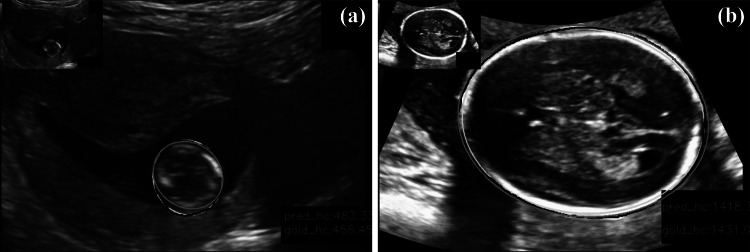

The fetal skull is not fully developed in the first trimester of pregnancy, so it is challenging for fetal head segmentation from ultrasound images in this trimester. The proposed method achieved generally better segmentation performance for the second and third trimesters of pregnancy. From experiments, we found two challenges for the proposed method. First, the DSC of the proposed method in the early pregnancy was relatively lower, as shown in Fig. 10a. From the training set images, we found that part of the fetal skull in the early pregnancy has not developed, and the skull contour is small, with noise which may affect image segmentation performance. The second was that the AD was generally larger in the third trimester of pregnancy, as shown in Fig. 10b. We considered two possible reasons. (i) Because the fetal skull grows increasingly at late pregnancy, it may be difficult to capture a complete structure on an ultrasound imaging plane, resulting in partial loss of the skull at the two ends, so the fitted ellipse may be significantly larger. (ii) The edge structure of fetal skull is obviously thicker at the third semester, meaning that there are more, brighter pixels at the skull with high echogenicity. Some of these pixels on the thick skull may cause misclassification, as the computer-detected fetal head boundary is a thinner ellipse curve (Fig. 10b).

Fig. 10.

Challenges in fetal ultrasound image segmentation by the proposed deeply supervised attention-gated V-Net method (blue: fetal head contours obtained by the proposed method, green: fitted ellipses, red: gold standard). a First semester of pregnancy. b Third semester of pregnancy